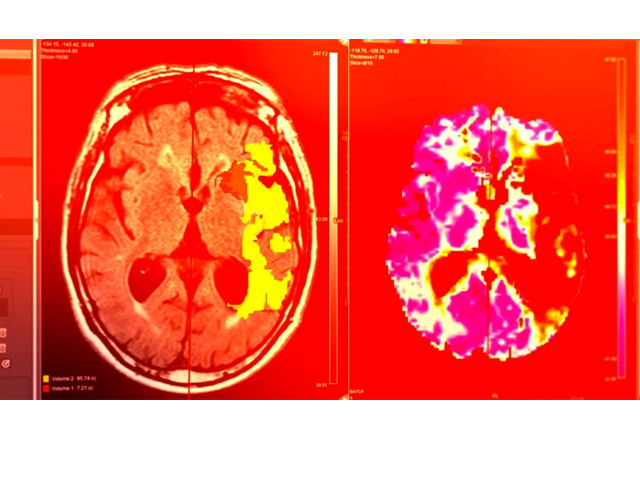

Michalis Papadakis, CEO de Brainomix, cuya tecnología ya está entrando a los hospitales para ayudar a los médicos, dice que hay un enorme potencial para mejorar los resultados con pacientes que hay tenido un ACV.

“Actualmente, cada 30 minutos un paciente con ACV, que podría haber sido salvad, muerte o queda permanentemente inhabilitado, no por el accidente cerebro-vascular, sino porque es admitido en un hospital que carece de la experiencia para diagnosticar y dseleccionar al paciente para un tratamiento que le salve la vida”.

Su producto, desarrollado con datos extraídos de miles de tomografías, ayuda a los médicos a interpretar las imágenes y tomar rápidamente las decisiones necesarias cuando se sospecha que el paciente ha tenido un ACV.